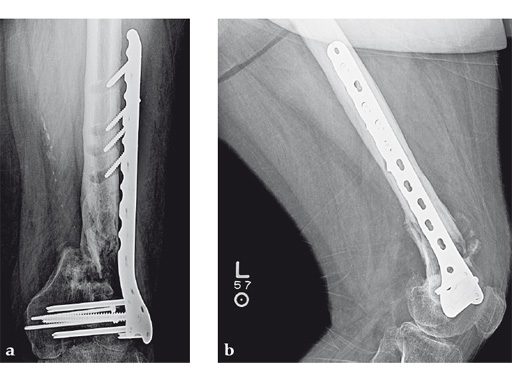

Case 3: A 53-year-old man with hypotestosteronism, low vitamin D levels, and calcium metabolism problems. Recalcitrant atrophic nonunion of his distal femur after three surgical attempts with an extension and flexion contracture of his knee.

The VA-LCP Curved Condylar Plate was used to avoid previous enlarged screw holes and allow for stable fixation in the patient's osteoporotic distal segment. Secondary to his metabolic and mechanical problems, the decision was made to proceed with an endosteal implant and place interlocking screws through that implant from the VA-LCP Curved Condylar Plate. The combination of the retrograde/antegrade femoral nail and VA-LCP provides a very stable mechanical environment for the expected prolonged healing response.